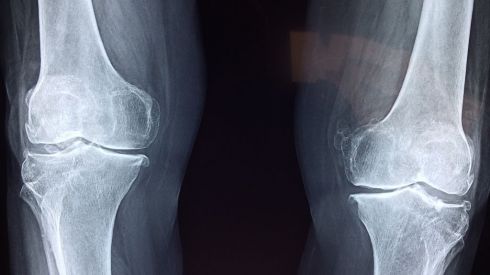

Что необходимо знать об остеоартрите

Остеоартрит - это форма артрита, вызванная воспалением, расстройством и возможной потерей хряща в суставах

Что нужно знать о повреждении хряща и методах лечения

Люди с повреждением хряща обычно испытывают боль в суставах, скованность и воспаление (отечность)